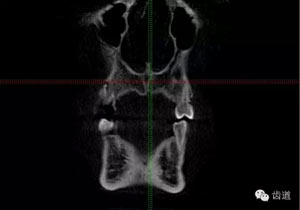

好的開始就是成功的一半。通過CBCT了解根管的位置,形態(tài),方向。

檢查顯示:近頰及腭根充填恰填,遠(yuǎn)頰根管內(nèi)有少許充填物影像。根尖明顯低密度影像。

處理:顯微根管治療。放置橡皮障,去除暫封,顯微鏡下超聲去除頰側(cè)根管上段部分牙本質(zhì),探及遠(yuǎn)中根管口,見有糊劑遮蓋。Path file根管疏通,M Two根管預(yù)備至2506#,配合3%次氯酸鈉和17%EDTA超聲蕩洗,干燥根管,放置氫氧化鈣糊劑,zoe暫封。